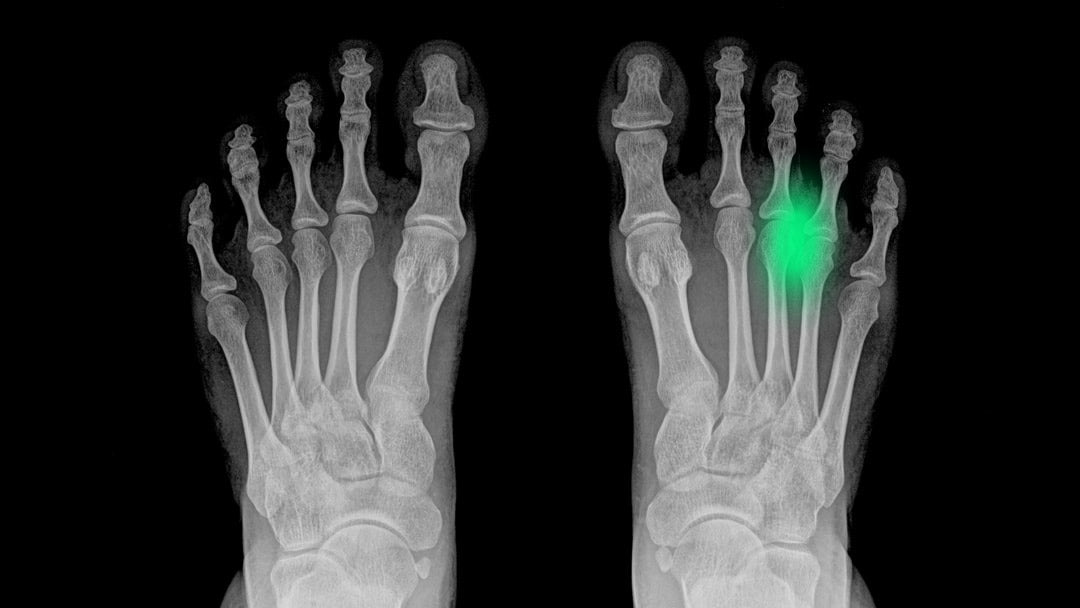

¿Qué es el neuroma de Morton?

El neuroma de Morton es una patología nerviosa que afecta al nervio interdigital plantar, normalmente entre el tercer y cuarto dedo del pie. Es un engrosamiento del tejido que rodea al nervio debido a una irritación o compresión repetitiva.